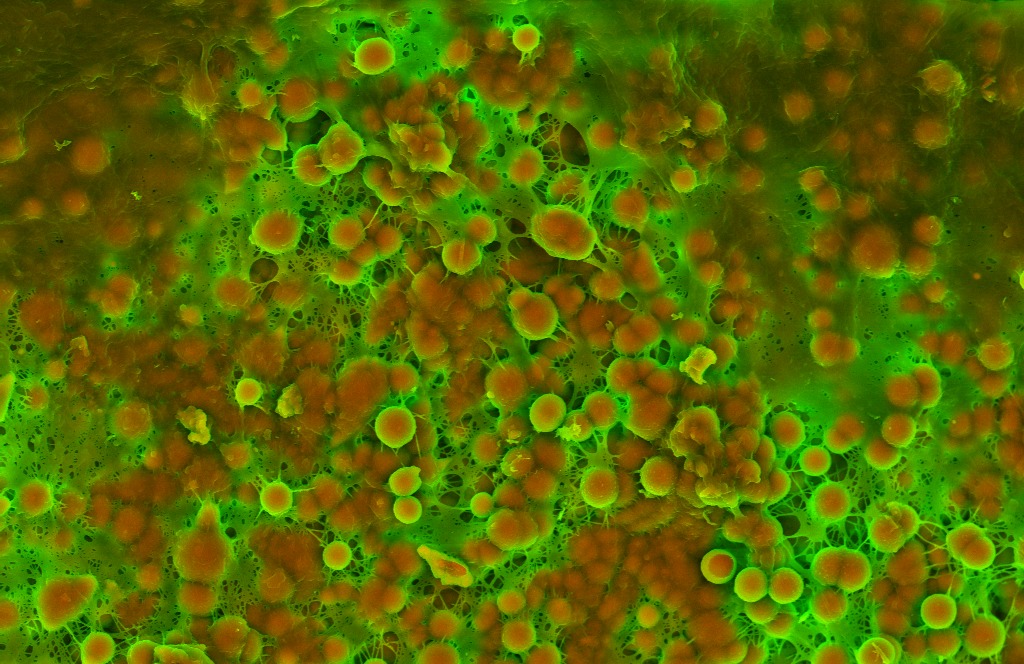

Histology classically shows reactive histiocytes with slender, wavy nuclei are known as Anitschkow cells, Aschoff bodies, gigantic cells, and fibrinoid material.